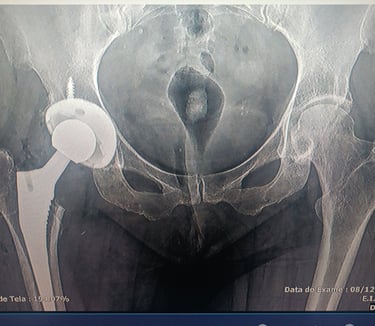

- Tratamento cirúrgico de fraturas ( transtrocanteriana, subtrocanteriana, diafisária de fêmur, acetábulo )

- Cirurgias de quadril ( prótese de quadril, síndrome do impacto, osteonecrose da cabeça do fêmur, síndrome do piriforme )